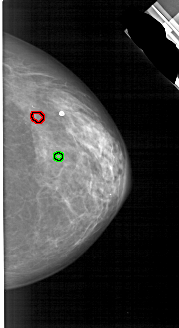

A_1791_1.LEFT_MLO

LEFT_MLO LINES 5356 PIXELS_PER_LINE 2626 BITS_PER_PIXEL 12 RESOLUTION 43.5 NON_OVERLAY

FILE: A_1791_1.RIGHT_MLO.OVERLAY

TOTAL_ABNORMALITIES 1

ABNORMALITY 1

LESION_TYPE CALCIFICATION TYPE PLEOMORPHIC DISTRIBUTION CLUSTERED

ASSESSMENT 4

SUBTLETY 2

PATHOLOGY BENIGN

TOTAL_OUTLINES 1

BOUNDARY

ABNORMALITY 2